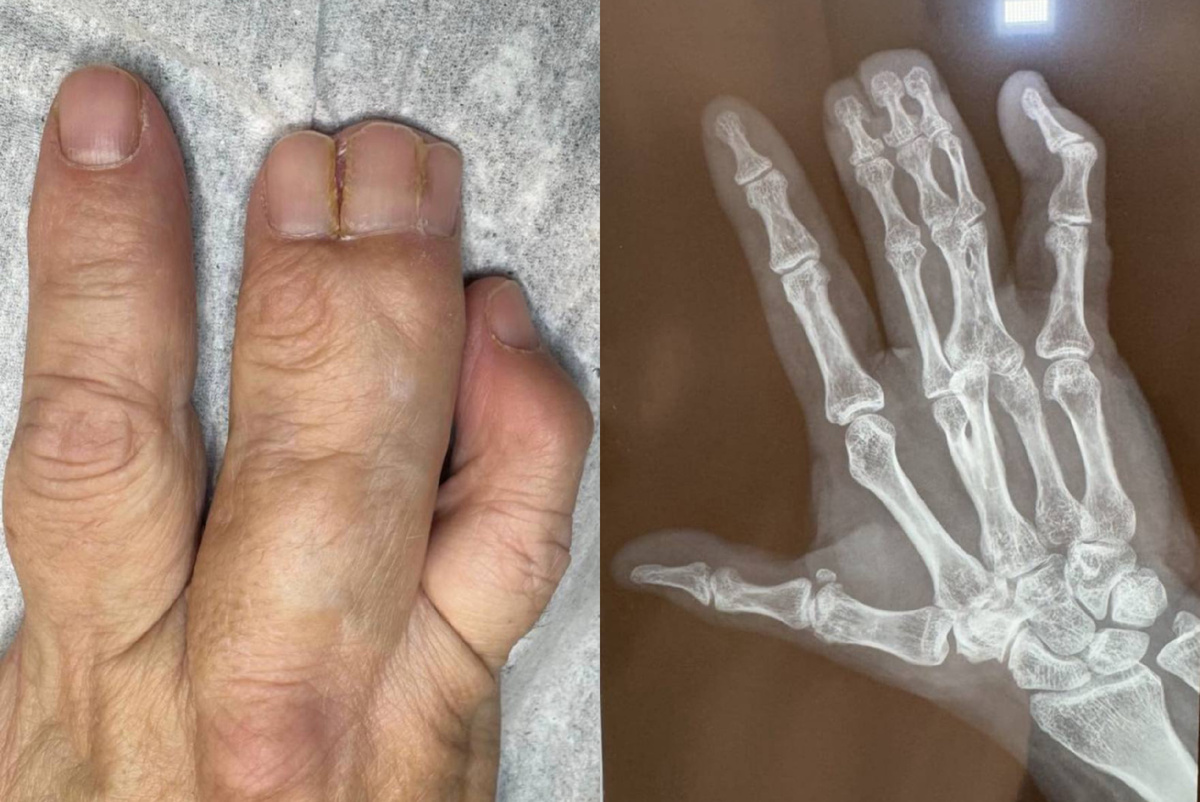

Синдактилия – это интересный и в то же время сложный медицинский термин, обозначающий врожденный или приобретенный порок развития конечностей. При этом два или более пальцев на кистях или стопах могут срастаться как полностью, так и частично. В этом статье мы подробнее рассмотрим причины, виды и способы лечения синдактилии.

Синдактилия классифицируется по нескольким критериям:

➖ Тип соединения: Соединение пальцев может происходить в виде тонкой перепонки – кожной перемычки, которая может охватывать всю длину пальцев. Также возможно сращение, при котором вовлечены мягкие ткани, кровеносные и лимфатические сосуды, а также нервные окончания.

➖ Длина сращивания: Сращение может происходить по всей длине пальцев или затрагивать одну или две фаланги, включая соединительные или костные ткани.

➖ Кожный мешочек: В некоторых случаях несколько пальцев могут оказаться в одном «кожном мешочке», при этом все фаланги развиты, и даже имеются ногти.

Синдактилия нередко сопутствует другим патологиям, таким как полифалангия или полидактилия, что усложняет процесс диагностики и лечения.